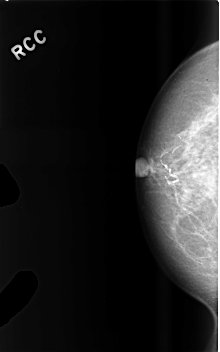

C_0476_1.RIGHT_MLO

RIGHT_CC LINES 4568 PIXELS_PER_LINE 2856 BITS_PER_PIXEL 12 RESOLUTION 50 NON_OVERLAY